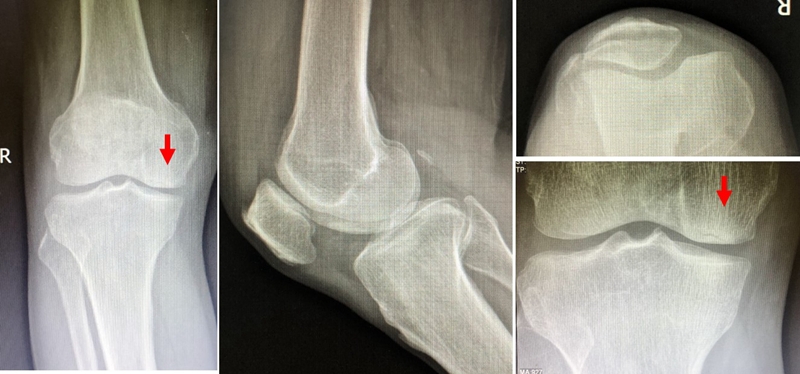

X线+MRI:通过测量正位X线片和MRI判断坏死区域的大小。

目前SONK诊断最常用的分期方法是1979年Koshino提出的分期法。Koshino分期基于临床和影像学的结果,将SONK分为四个阶段:

Ⅰ期:患者有膝关节症状,但影像学正常;

Ⅱ期:X线显示负重区变平,软骨下信号升高,周围有骨硬化;

Ⅲ期:受影响区域扩大和软骨下塌陷;

Ⅳ期:病变周围骨硬化和髁突周围骨赘形成的退行性阶段。

1979年Koshino分期